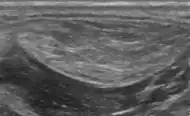

A physical exam is typically the easiest way to diagnose it. Rarely, a tissue biopsy or imaging may be required. The imaging modality of choice is magnetic resonance imaging (MRI) because it has superior sensitivity of distinguishing it from liposarcoma as well as mapping the surrounding anatomy.[22]

Medical ultrasonography of a lipoma in the thenar eminence: It is hyperechoic compared to adjacent muscle, and relatively well-defined, with miniature hyperechoic lines.[23] -